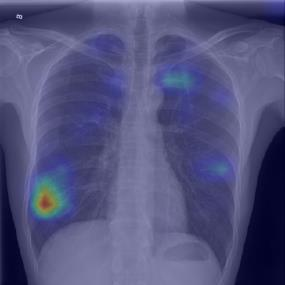

Chest X-ray (CXR) is the most typical diagnostic X-ray examination for screening various thoracic diseases. Automatically localizing lesions from CXR is promising for alleviating radiologists' reading burden. However, CXR datasets are often with massive image-level annotations and scarce lesion-level annotations, and more often, without annotations. Thus far, unifying different supervision granularities to develop thoracic disease detection algorithms has not been comprehensively addressed. In this paper, we present OXnet, the first deep omni-supervised thoracic disease detection network to our best knowledge that uses as much available supervision as possible for CXR diagnosis. We first introduce supervised learning via a one-stage detection model. Then, we inject a global classification head to the detection model and propose dual attention alignment to guide the global gradient to the local detection branch, which enables learning lesion detection from image-level annotations. We also impose intra-class compactness and inter-class separability with global prototype alignment to further enhance the global information learning. Moreover, we leverage a soft focal loss to distill the soft pseudo-labels of unlabeled data generated by a teacher model. Extensive experiments on a large-scale chest X-ray dataset show the proposed OXnet outperforms competitive methods with significant margins. Further, we investigate omni-supervision under various annotation granularities and corroborate OXnet is a promising choice to mitigate the plight of annotation shortage for medical image diagnosis.